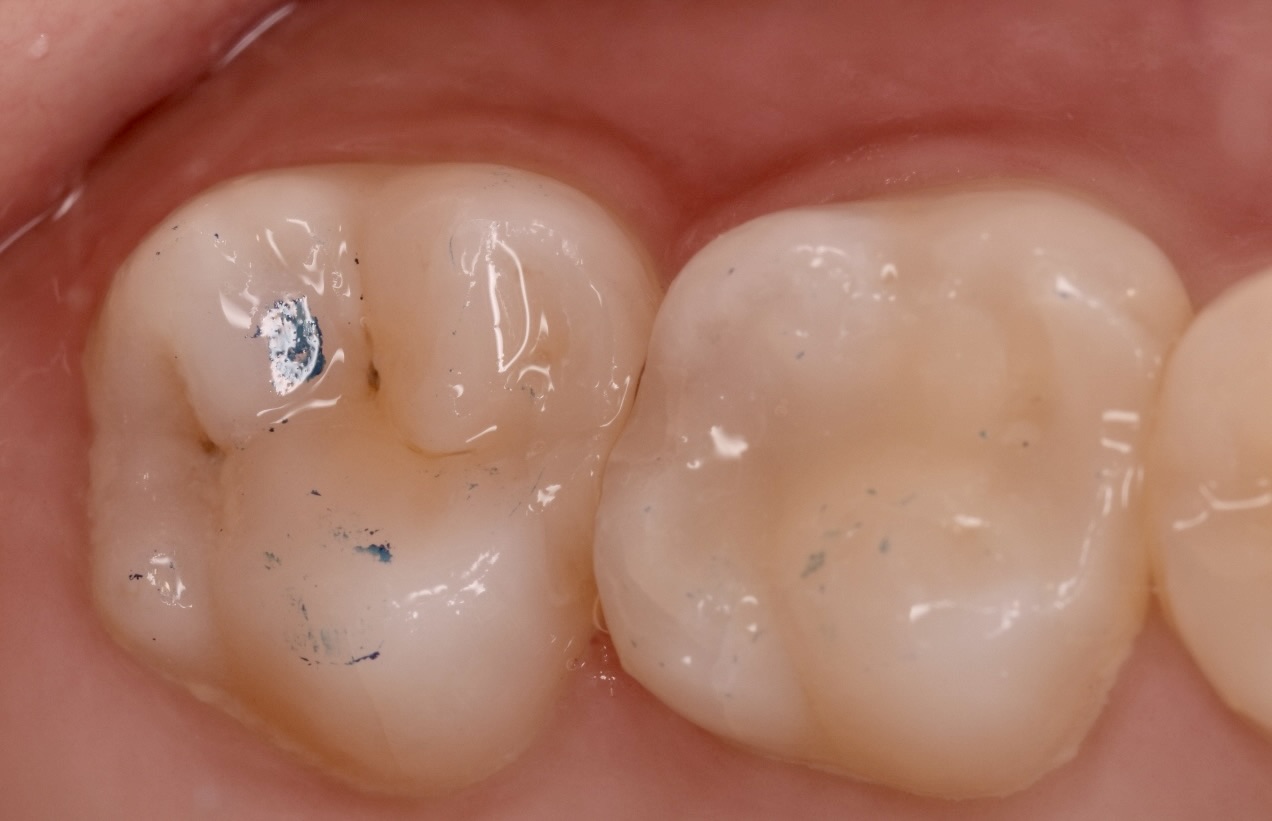

術後

術後レントゲン 術後口腔内

精密根管治療により感染源を除去。症状は消失し、機能的にも問題なく経過しております。